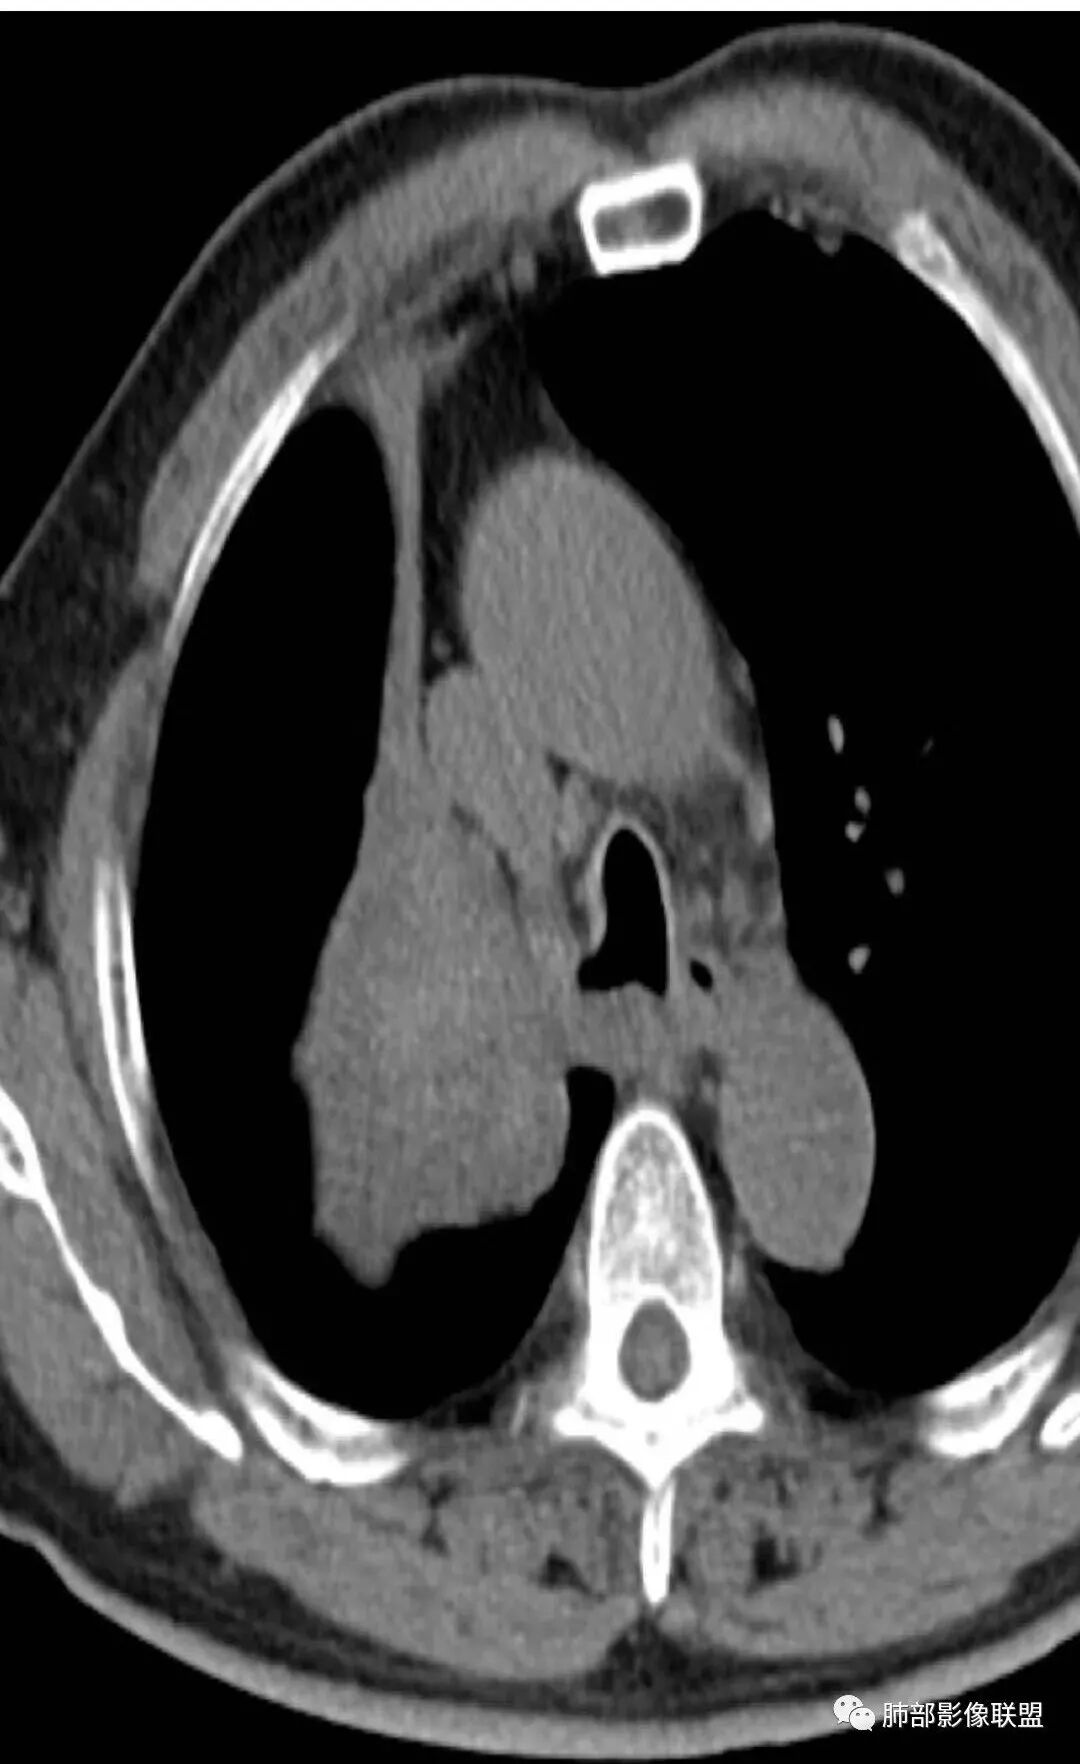

影像:影像右侧大支气管阻塞,临床没有症状或很轻微,要想到胃腺癌转移;胸壁代偿好,透亮度稍低不明显,慢性过程;34.8-52.5HU,主病灶支气管前壁另有1结节,都做成增强两期了,动脉期较平扫有强化;

晨读:患者老年男性,以咳嗽一月就诊,少量白痰,胸CT:纵隔右移,右肺体积缩小,气管下段管壁可见结节样改变,气管软骨变形,气管下段及右主支气管可见新生物向管壁浸润,并向管腔外生长,右上肺肺不张,但不张边缘可见病灶呈膨胀性生长,可见分叶,增强后强化明显。考虑:肺部恶性病变(鳞癌?)

右肺上叶肿块,边缘光滑,略膨隆,近段支气管堵塞,平扫密度均匀,增强后不均匀强化,其内可见不规则血管和坏死,纵隔淋巴结肿大,老年男性,无感染性病史,综合考虑恶性肿瘤(鳞癌,腺癌),鉴别:OP(一般下叶多见)

从强化情况和冠状位看主要还是从外向内的一个肿块,有不张,但不张范围不大,近端支气管堵塞,考虑腺癌或类癌(原发或转移都可能),鉴别鳞癌。

@曹坤,河北保定清苑区人民医院ct室 肿块大,阻塞和不张范围小,强化这么大肿块没有明显坏死,鳞癌这样相对少见了

1.右肺上叶较大块影,密度不均,轻度强化并见低密度区,所属支气管截断并腔内突入,是符合肺鳞癌的影像学特征和生物学行为的。

2.胃癌常会首先胃旁淋巴结、腹主动脉淋巴结转移,肝脏血行转移,以及双肺多发转移,本例孤立右肺上叶病灶巨大,多有不符。

3.胃癌多血供,患者肺内病灶轻度强化。